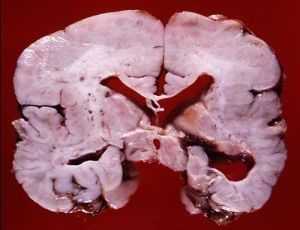

Фото мозга в разрезе и на МРТ ребенка с диагнозом агирия

- Агирия (лиссэнцефалия) - аномалия формирования коры головного мозга, при которой извилины недоразвиты, слабо выражены, либо отсутствуют, архитектоника коры нарушена. Внешний вид головного мозга ребенка идентичен внешнему виду мозга плода на 3-4 месяце пренатального периода. Агирия является тяжелой формой лиссэнцефалии. Может быть как идиопатическим заболеванием, так и сопровождать другие патологии (синдром Миллера-Дикера, синдром Нормана-Робертса, синдром Уокера-Варбурга, врожденную мышечную дистрофию Фукуямы).